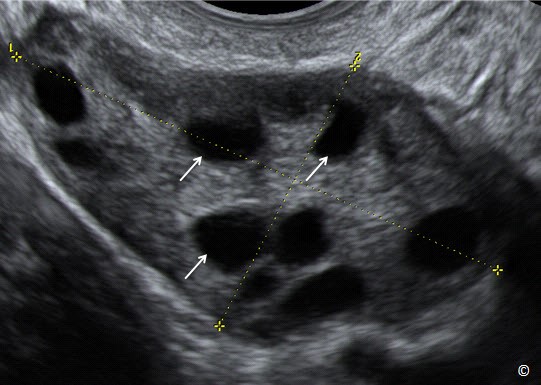

Buồng trứng đa nang (PCOS) là tình trạng rối loạn nội tiết tố nữ, khiến buồng trứng xuất hiện nhiều nang nhỏ nhưng không thể phát triển và rụng trứng bình thường.